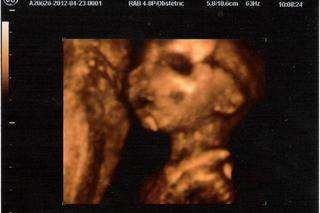

tak troska to zhrniem od vtedy co som tu nepisala...boli sme uz aj v nemocnici,,,na konci 21. tt mi robil lekar velke sono a spravil mi jednu 3D fotecku na ktorej je nase male dievcatko s menom Zara Izabell...konecne sme sa s manzelom dohodli na mene...na 3D idem na konci 25. tt tak uz sa s manzelom tesime...mala kopka najviac vecer ked si lahnem k telke...toto iste robila aj nasa prva babulka...inak na foto co som prilozila sa nase mimi podoba velmi na nasu prvu kocku tak som zvedava🙂

kamoska mi hovorila ze aky bol jej malicky na 3D cku taky bol presne aj ked sa narodil tak som zvedava🙂